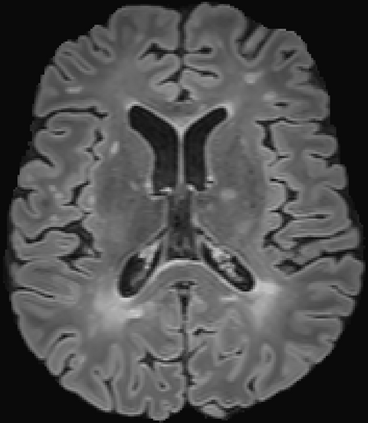

Assessment of lesions and their longitudinal progression from brain magnetic resonance (MR) images plays a crucial role in diagnosing and monitoring multiple sclerosis (MS). Machine learning models have demonstrated a great potential for automated MS lesion segmentation. Training such models typically requires large-scale high-quality datasets that are consistently annotated. However, MS imaging datasets are often small, segregated across multiple sites, with different formats (cross-sectional or longitudinal), and diverse annotation styles. This poses a significant challenge to train a unified MS lesion segmentation model. To tackle this challenge, we present SegHeD, a novel multi-dataset multi-task segmentation model that can incorporate heterogeneous data as input and perform all-lesion, new-lesion, as well as vanishing-lesion segmentation. Furthermore, we account for domain knowledge about MS lesions, incorporating longitudinal, spatial, and volumetric constraints into the segmentation model. SegHeD is assessed on five MS datasets and achieves a high performance in all, new, and vanishing-lesion segmentation, outperforming several state-of-the-art methods in this field.